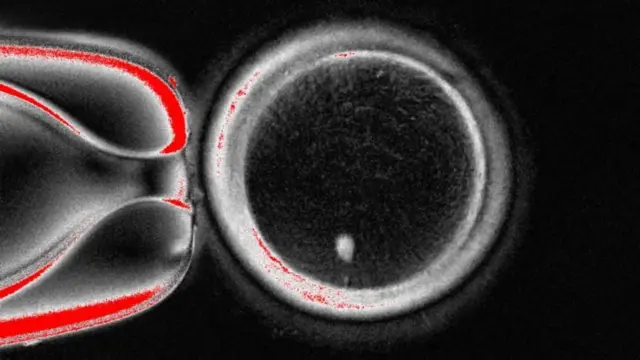

Saayintistoonni Ameerikaa miciree dhala namaa sadarakaa jalqabaarra jiru DNA seelii gogaa namaarraa fudhatame isparmii waliin makuun tolchan.

Yunivarsiitii Fayyaafi Saayinsii Oriigan keessatti gareen qorannoo kuni seelii gogaa namaa irraa niwkilasii fudhate. Niwkilasiin kunis odeeffannoo qaccee sanyii guutuu kan qabate dha.

Kanaan booda hanqaaquu arjoomaan kenname garuu qajeelfamooti qaccee sanyii irraa kaafaman keessa kaa'ama.

Haa tahu malee hanqaaquun seelii gogaa fudhate kuni cimdii kiroomoozoomii guutuu waan qabuuf isparmiin waliin fertilaayizeeshinii uumuuf qophii miti.

Namni tokko cimdii DNA kan haadhaafi abbaa irraa 23, 23dhaan 46 fudhatee dhalata kana jechuun hanqaaquun kuni hundasaa qaba jechuu dha.

Kanaaf sadarkaan itti aanu hanqaaquun haaraa kuni kiroomoozoomiisaa 23 akka gatu gochuu dha, adeemsi kuni mitoomiyoosiis jedhama.

Qorannoon joornaalii Nature Communications jedhamu irratti bahe akka agarsiisu adeemsa kanaan hanqaaquun fayyaa 82 uumamuu danda'eera. Kunneenis isparmiidhaan yoo walitti makaman gara micireetti kan guddatan yoo tahu guyyaa jaharra darbuu garuu hin dandeenye ture.